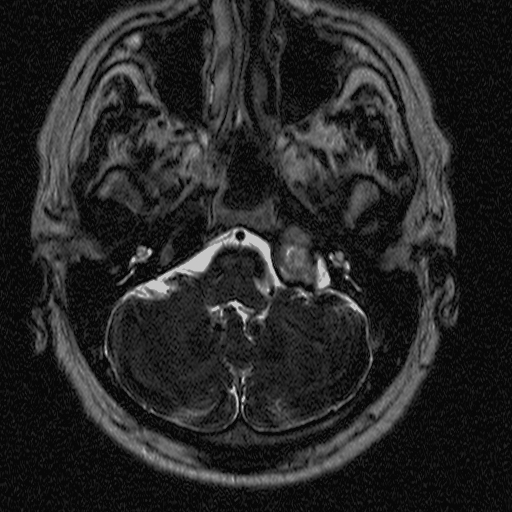

4. image: Young male patient with a left supraclavicular lump. Upper panel: complex cystic mass with sepatations; normal flow in the neighbouring vessels. Lower panel: T2W, postcontrast T1W, fat-saturation T1W MRI suggest cystic lymphangioma (Asklepios Klinik Altona, Hamburg)